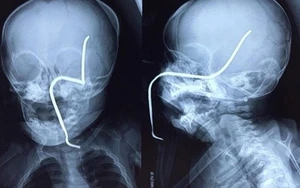

Một bé gái bị thanh sắt rỉ đâm thủng sọ

Trong lúc đang chơi gần nhà, bé N.T.H (8 tháng tuổi, ở Sơn Tây, Hà Nội) bị chiếc máy đang cắt cỏ gần đó bắn văng thanh sắt rỉ nằm ẩn dưới cỏ vào má trái, xuyên thủng hộp sọ.